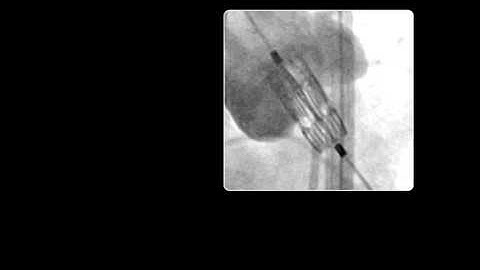

Valve Deployment via Fluoroscopy